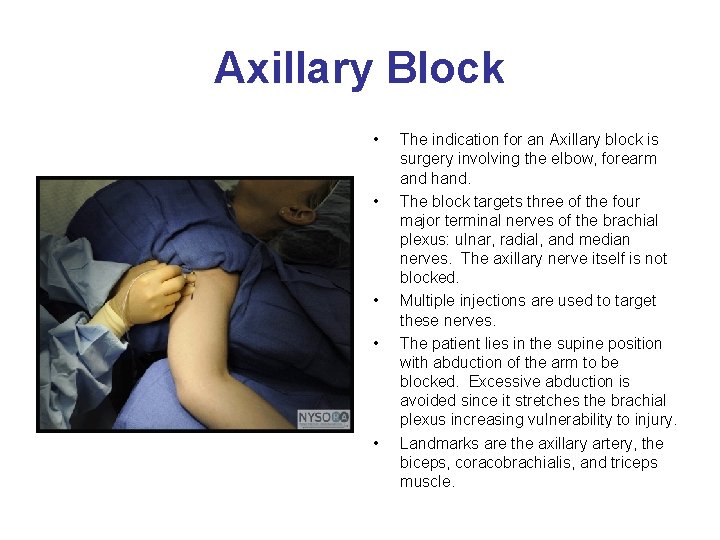

Axillary Block • • • The indication for an Axillary block is surgery involving the elbow, forearm and hand. The block targets three of the four major terminal nerves of the brachial plexus: ulnar, radial, and median nerves. The axillary nerve itself is not blocked. Multiple injections are used to target these nerves. The patient lies in the supine position with abduction of the arm to be blocked. Excessive abduction is avoided since it stretches the brachial plexus increasing vulnerability to injury. Landmarks are the axillary artery, the biceps, coracobrachialis, and triceps muscle.